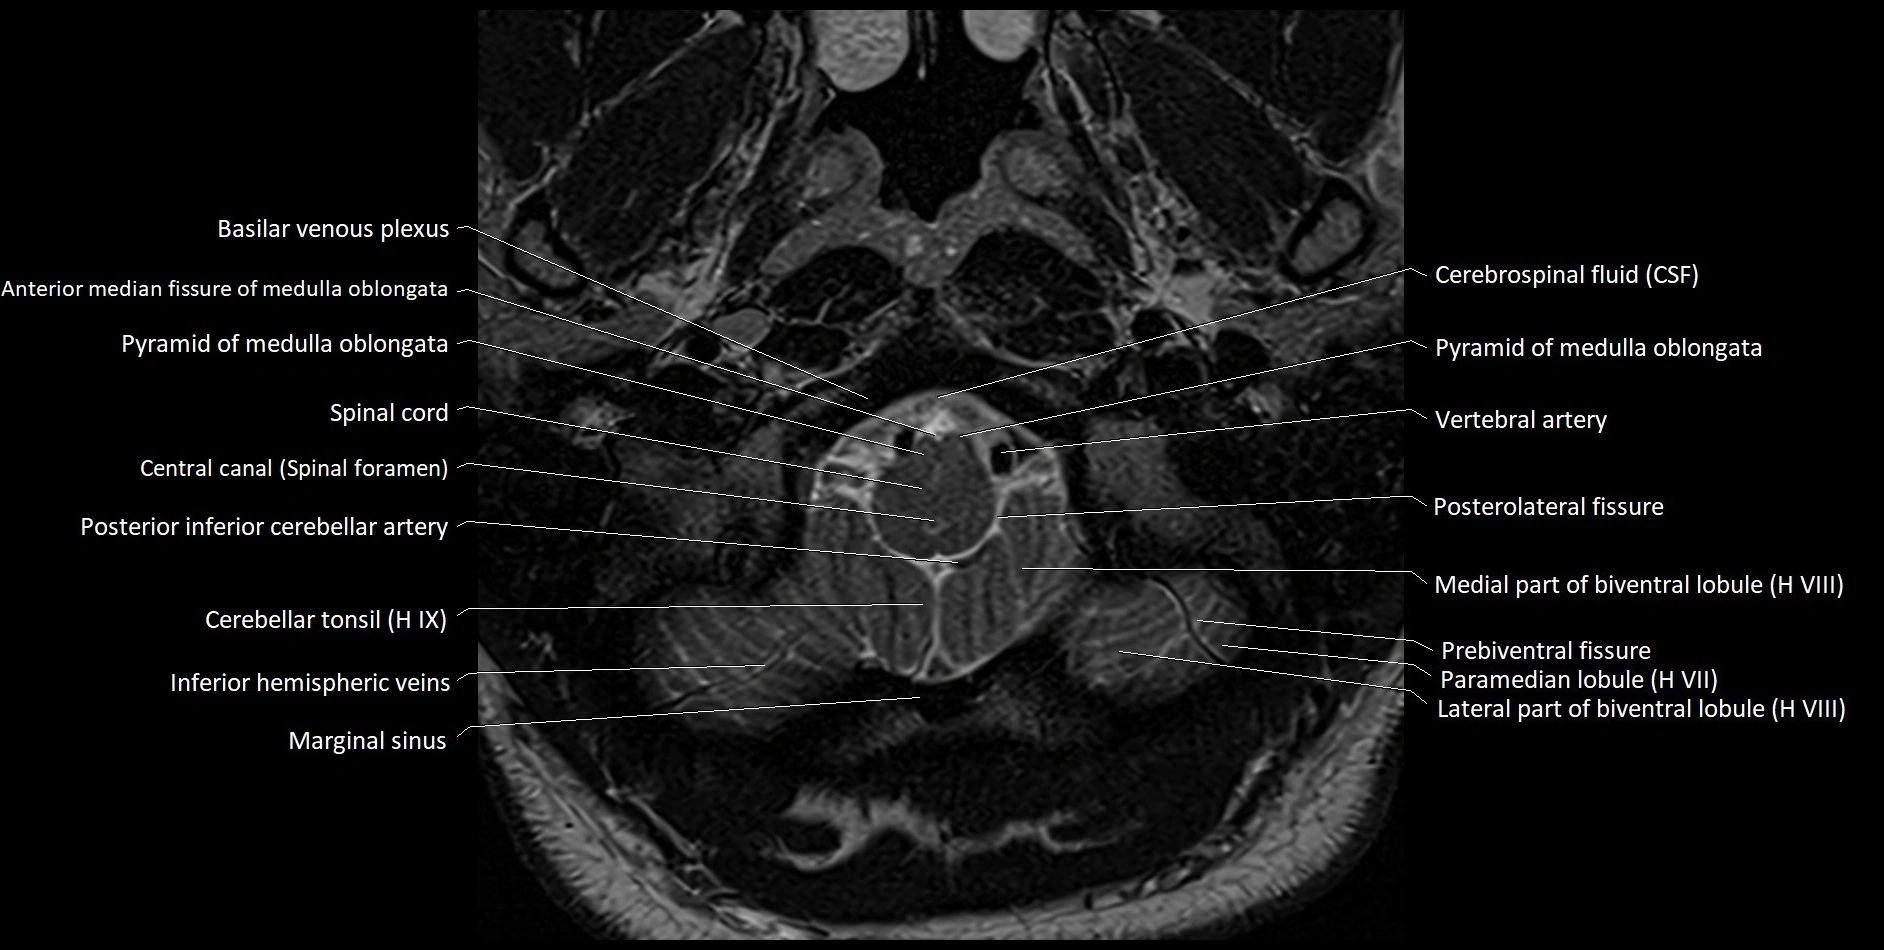

Experience the next generation of cross-sectional anatomy with our advanced 3T MRI, enhanced by AI-powered Deep Resolve reconstruction. Our ultra-high-resolution imaging (0.3–0.7 mm in-plane resolution) combined with ultra-small field-of-view techniques reveals fine anatomical detail with exceptional clarity, redefining anatomical visualization and education.

Explore an advanced library of ultra-high-resolution MRI anatomy, developed from hundreds of repeated scans of volunteers using cutting-edge 3T scanners, dedicated coils, and AI-powered enhancement. These images capture real anatomical detail, revealing even the smallest microstructures while preserving the authenticity of true clinical imaging without over-reliance on virtual labeling.

All our cross-sectional images are meticulously hand-labeled by professionals with over 20 years of experience in cross-sectional imaging. This is the result of over six years of dedicated work, precision, and passion. Every image is individually checked and verified by senior consultant radiologists from major London NHS trusts, each with relevant subspecialty expertise—ensuring the highest level of accuracy and clinical relevance.